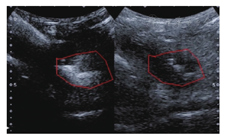

常规超声显示克罗恩病患者腹腔脓肿表现为累及的增厚肠壁旁局限性低回声区,形态不规则、内回声浑浊,可有高回声气体回声,壁不规则,囊壁及周围组织可见较丰富血流信号,液区内未见血流信号,可与病变肠段分界不清形成包块。静脉超声造影显示脓腔内无增强,周围炎性组织和病变肠段提示高增强。于腔内注入稀释造影剂在造影模式下可清晰地观察到脓腔的位置、大小及液化范围(图1)。根据文献系统综述提示,肠道超声对腹腔脓肿的检测具有与CT和MR相似的较高敏感度和高特异度[6,7],尤其对表浅的腹腔脓肿诊断效能更佳。

经腹腔内超声造影(intra-cavitary contrast-enhanced ultrasound,IC-CEUS)是在克罗恩病患者腹腔脓肿穿刺抽脓后将造影剂注入脓腔内,在造影模式下观察脓腔、瘘管、肠腔的情况,可用于对脓腔的观察和肠瘘的诊断(图1,图2)。本研究团队IC-CEUS均由有超声介入和超声造影经验丰富的超声医师操作。具体操作流程为超声引导下将21-gauge细针穿刺活检(fine needle aspiration,FNA)针(proCore,cook endoscopy,Winston-Salem,NC)置入克罗恩病病变累及肠段旁的脓腔行脓肿穿刺引流,再通过穿刺针注入10~30 ml的稀释超声造影剂声诺维(Bracco Co.,Ltd,Italy,diluted to 1∶300 with 0.9% saline)。在造影剂模式下观察并储存图像,对肠瘘瘘管和邻近器官的解剖关系进行实时评估。IC-CEUS图像评估得到以下信息:(1)确定瘘管的存在并分析其解剖学形态;(2)评估瘘管及其旁病变肠管的关系;(3)评估瘘管及其连接脓腔和其他腹部脏器(如累及膀胱)的关系。以手术病理诊断作为参考标准。